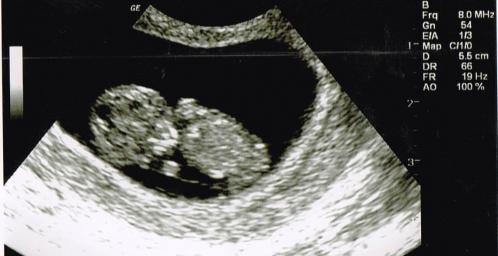

Baby is upside down, so can't guess :( It's a cutie :)

I know that it's upside down but still the bottom picture screams girl to me! Do you see what I'm saying?

bumping this.....The second one down looks girly? RIght????

Honestly, no...it doesn't really look girlie to me. I don't think you can tell anything at all by any of those pictures. For that age, you need a nub shot and you don't have one. Sorry.